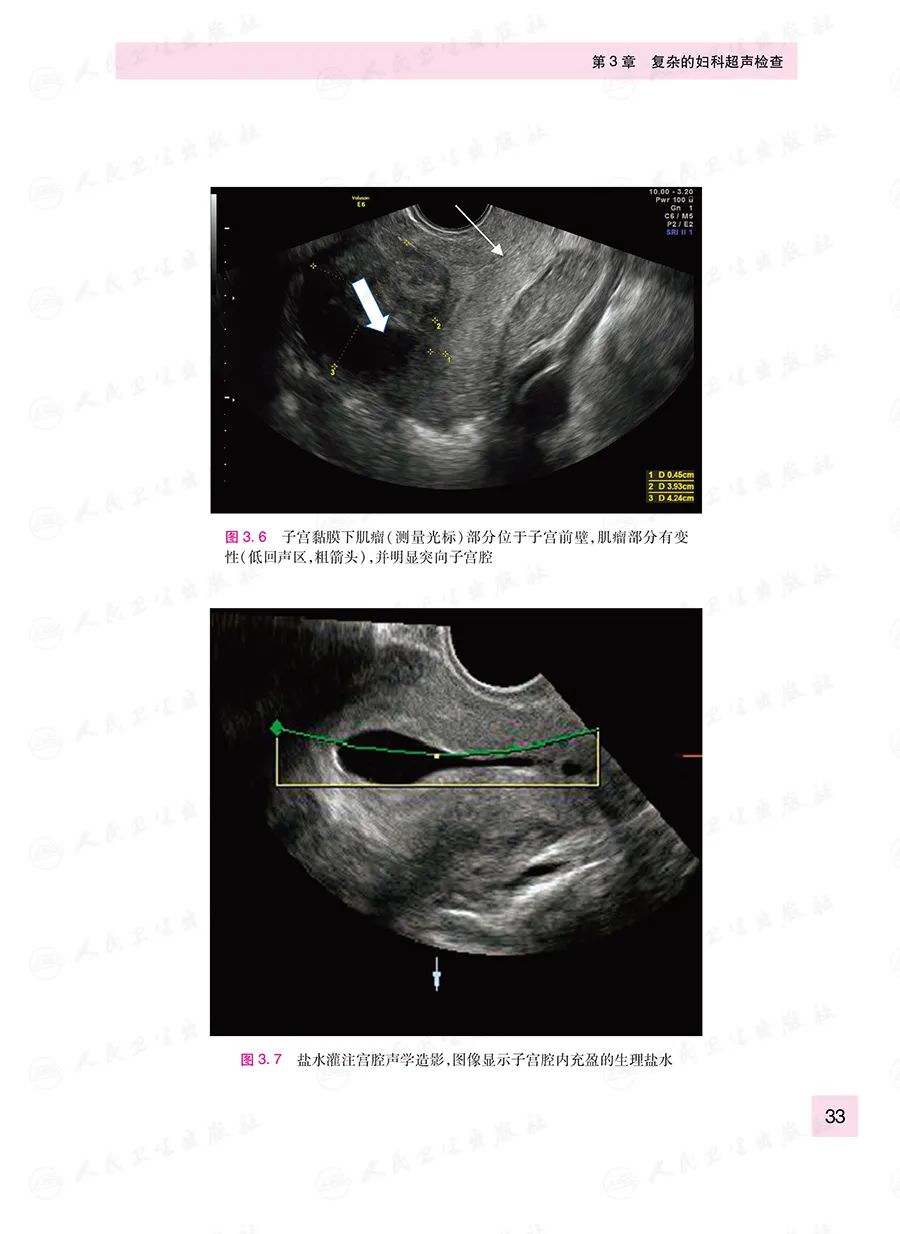

本书原著由英国妇科超声专家编写,定位于从事妇科超声工作的低年资医生,从妇科超声实际工作中仪器调节、操作手法、图像优化等基础知识讲起,进而对常见妇科疾病的超声诊断与鉴别诊断进行了归纳总结。全书强调实用性,以帮助读者了解日常工作中容易被忽略的细节问题,有助于读者快速掌握并提升临床诊断技能。本书各章节涵盖的主题全面,包括设备的熟悉,经阴道超声的操作原则,棘手的子宫和卵巢,与ART相关的超声评估等。书中讨论了二维和三维超声的应用,并阐述了如何优化图像质量,如何在具有挑战性的评估中获得有用的临床信息。大量的图像可以帮助读者熟悉正常的解剖结构和常见疾病。章节中的总结部分和基于疾病的病例展示也为评估病情和病变提供了有价值的参考。